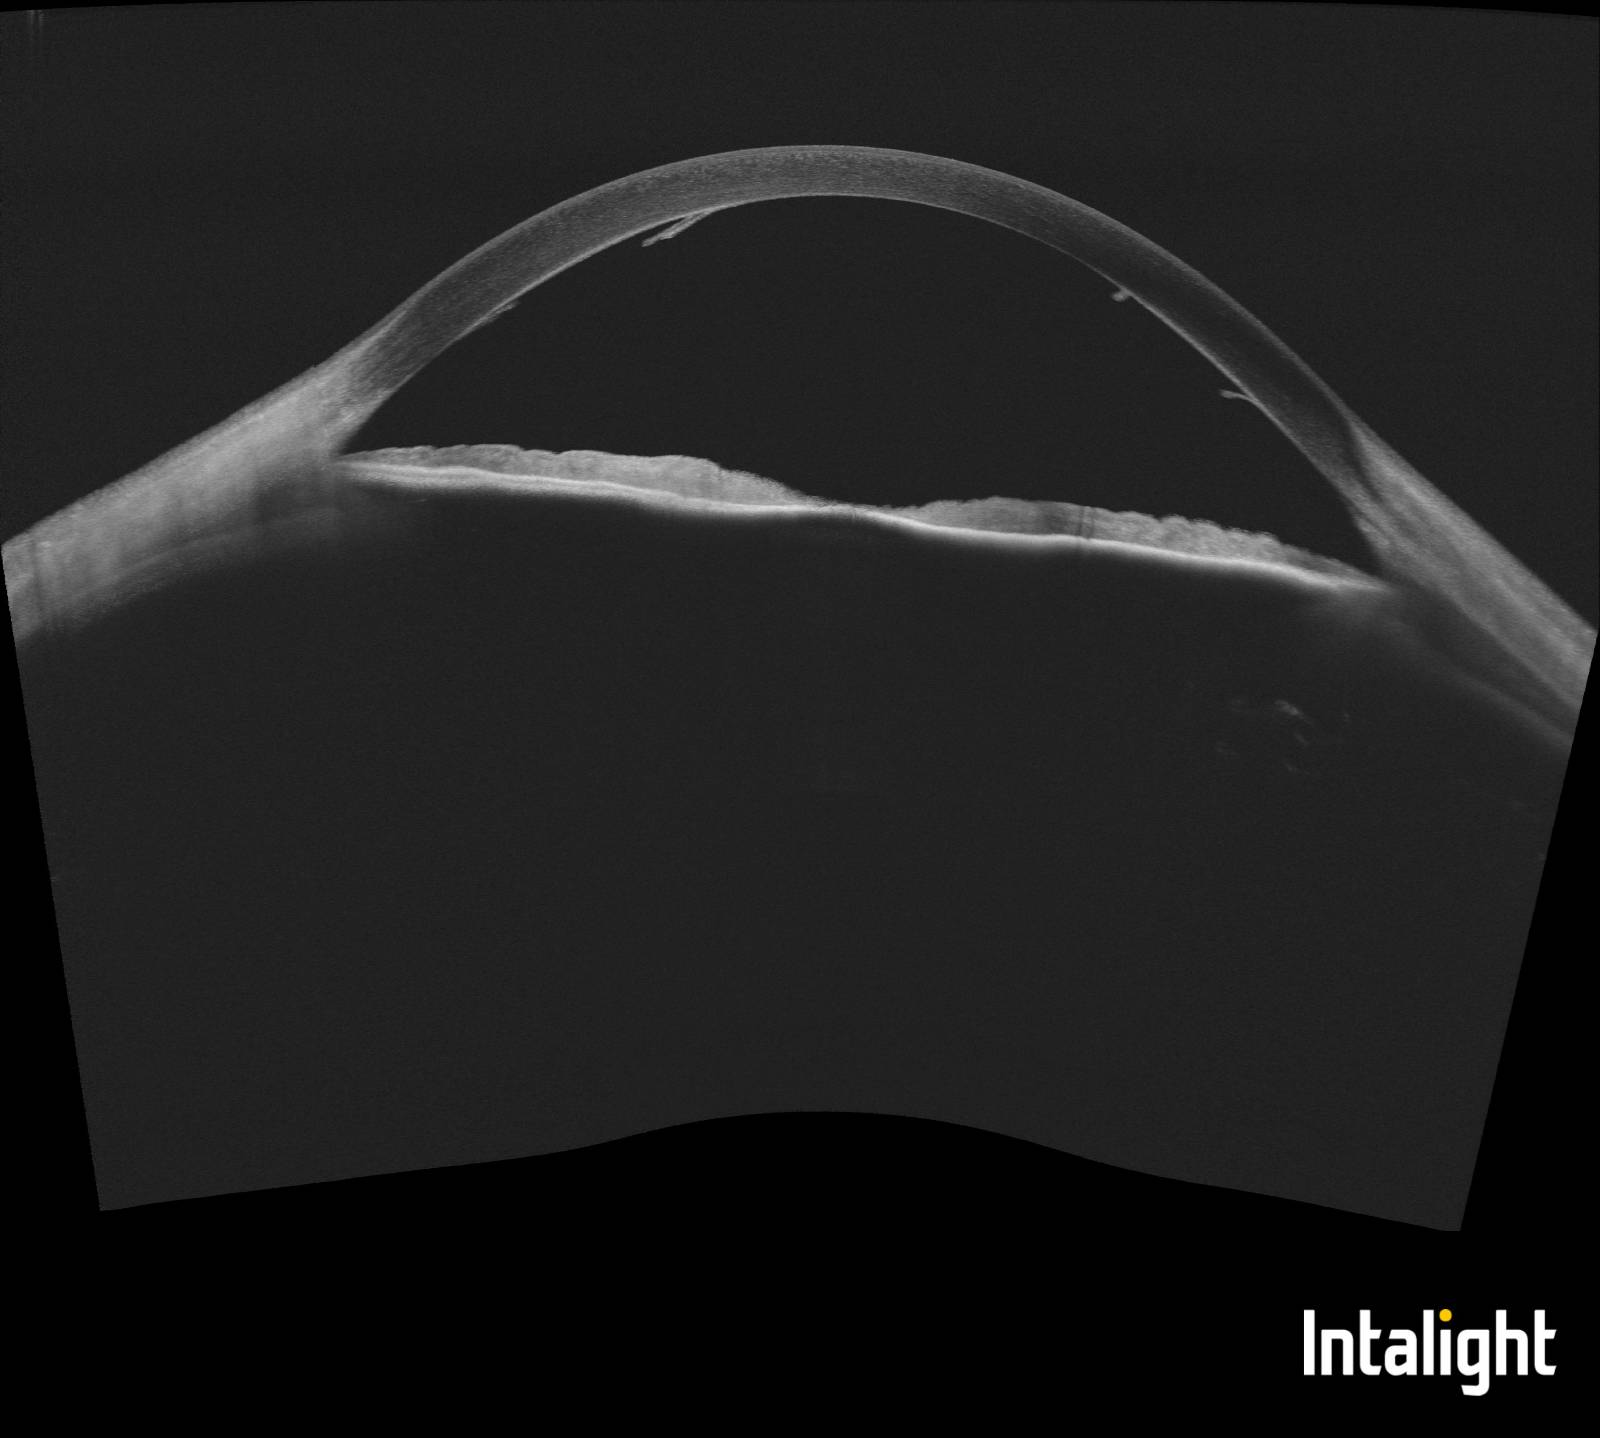

Uveitída - synechie po zápalových procesoch v oku

Synechie, zrasty dúhovky k rohovke alebo šošovke, zachytené pomocou štrbinovej lampy S390L.